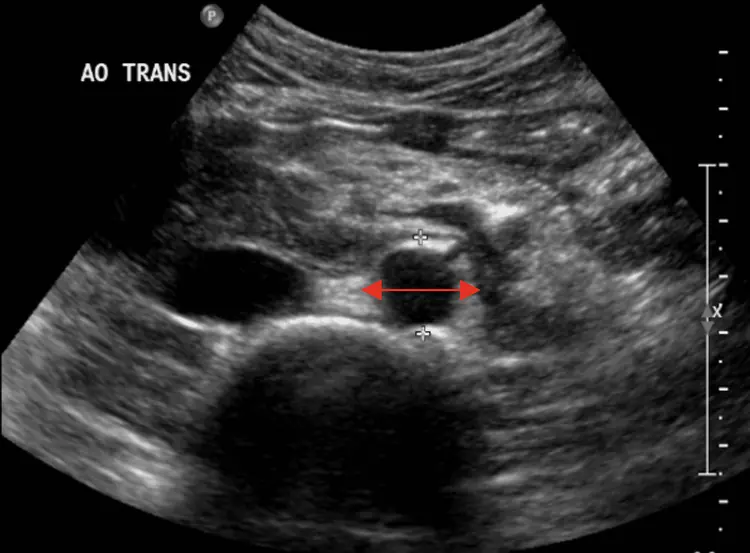

Voir lâaorte avant quâelle ne cĂšde.